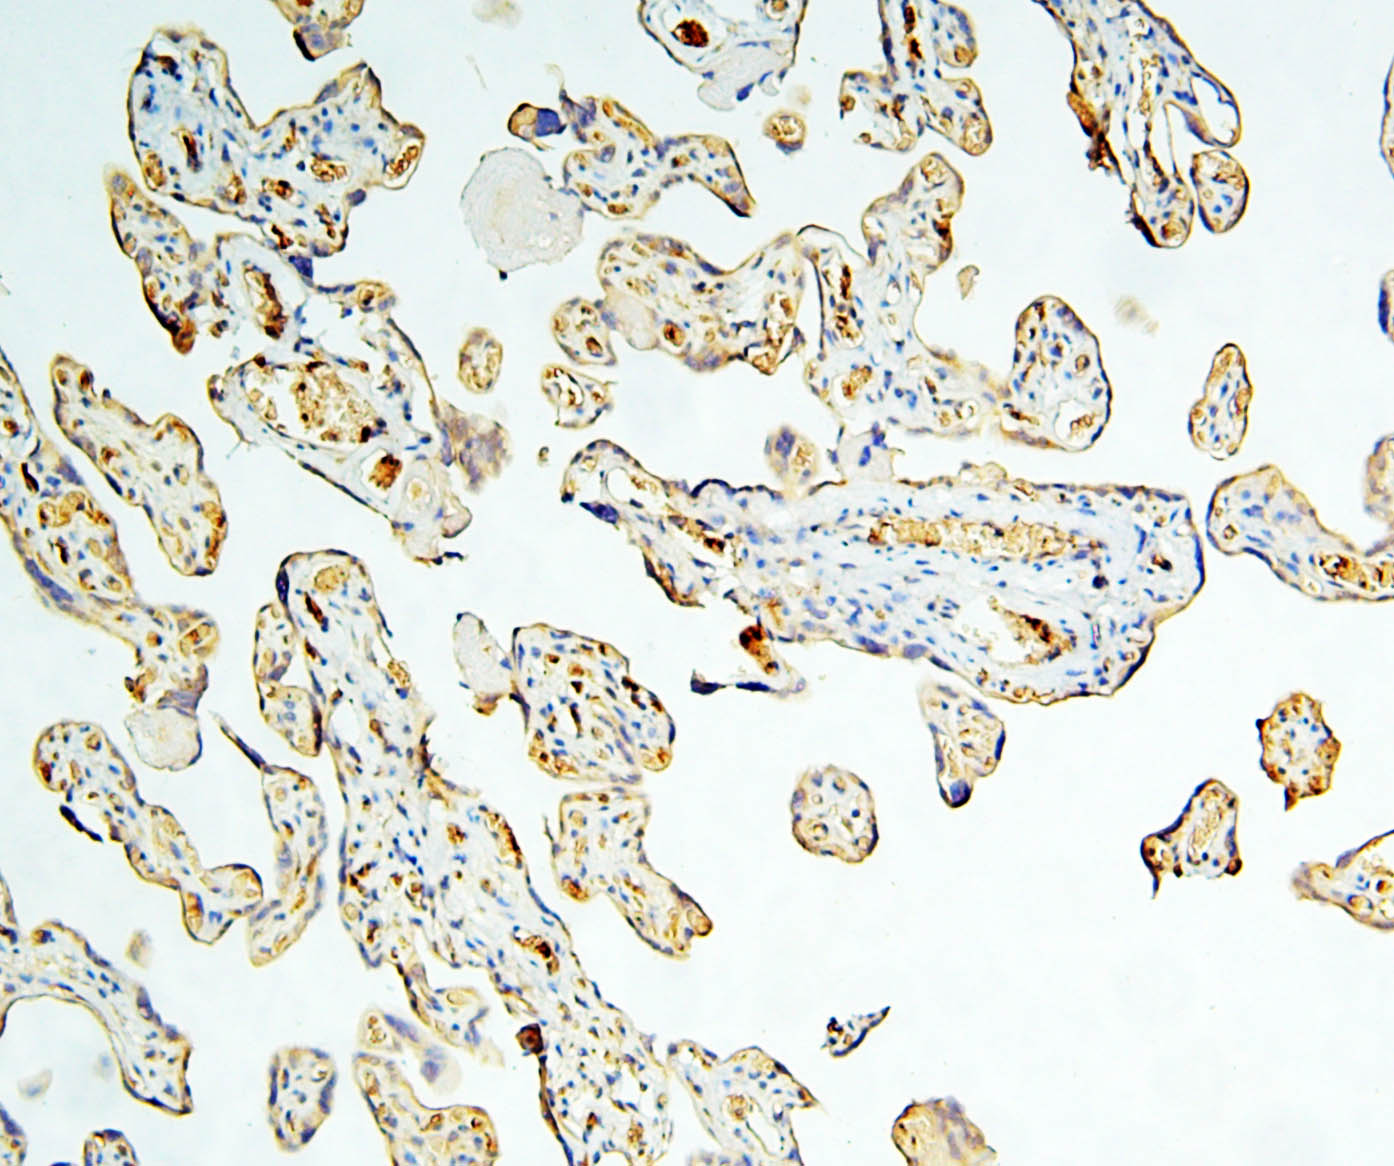

IHC analysis of Caspase 3/CASP3 (p17) using anti-Caspase 3/CASP3 (p17) antibody (M00334-7).

Caspase 3/CASP3 (p17) was detected in a paraffin-embedded section of human placenta tissue. Biotinylated goat anti-mouse IgG was used as secondary antibody. The tissue section was incubated with mouse anti-Caspase 3/CASP3 (p17) Antibody (M00334-7) at a dilution of 1:200 and developed using Strepavidin-Biotin-Complex (SABC) (Catalog # SA1021) with DAB (Catalog # AR1027) as the chromogen.